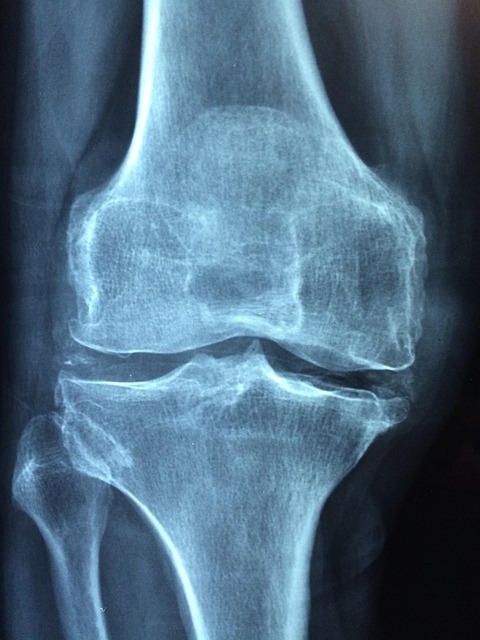

관절이란 뼈와 뼈가 만나는 부위입니다. 관절은 뼈 사이가 부드럽게 운동하도록 연골이나 인대 등의 구성으로 조직되어있고 움직임이나 충격에 따라 그것을 흡수하는 아주 중요한 역할을 합니다.

이러한 관절에 염증이 생긴 것을 관절염이라고 합니다.

관절염의 증상에는 굉장히 여러 가지가 존재합니다. 아무래도 연골이 있다 보니 나이가 들면 자연스레 약해지기 마련이죠. 그러나 폭발적인 운동을 하는 운동선수나 교통사고 등의 외부 충격이 크게 다가온 사람에게는 관절의 건강이 약해져 있을 수 있죠. 나이에 상관없이 이러한 증상이 있다면 병원에 내원하시는 것을 추천드립니다.